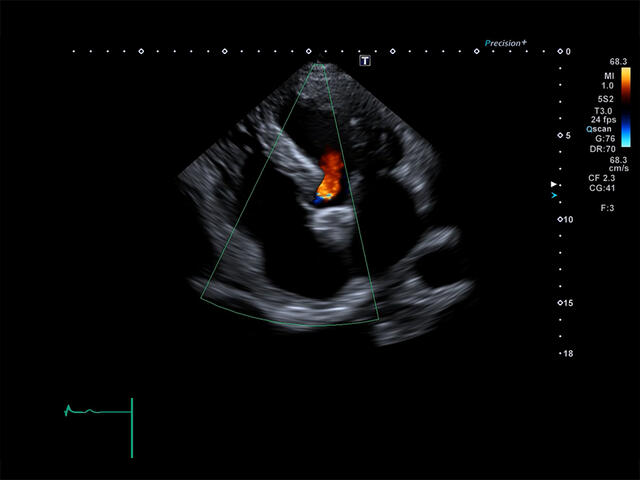

Отличная цветопередача с высокой детализацией и четкостью изображения. Устройство подходит для профессионального использования в частных кабинетах и крупных медицинских центрах. Комплектация сканера применима для самых разных исследований. Широкий диапазон прикладного клинического программного обеспечения высокоэффективен для общих исследований, сердечно-сосудистых, гинекологических, ортопедических, урологических.

Aplio a550 может работать с линейным матричным датчиком и поддерживает новейшие монокристаллические датчики. Также Aplio a550 поддерживает большое количество дополнительных опций, таких как - SMI, Компрессионная эластография, Эластография сдвижной волны, Smart Fusion, исследования с использованием контраста (CEUS), 3D реконструкции в реальном времени (4D), функции автоматической оценки подвижности миокарда и фракции выброса.

- Оценка глобальной и локальной сократимости ЛЖ сердца в 2D: 2D Wall Motion Tracking

- Стресс эхокардиография: Stress Echo

- Автоматические измерения в кардиологии - фракция выброса, объемы и пр. ✔